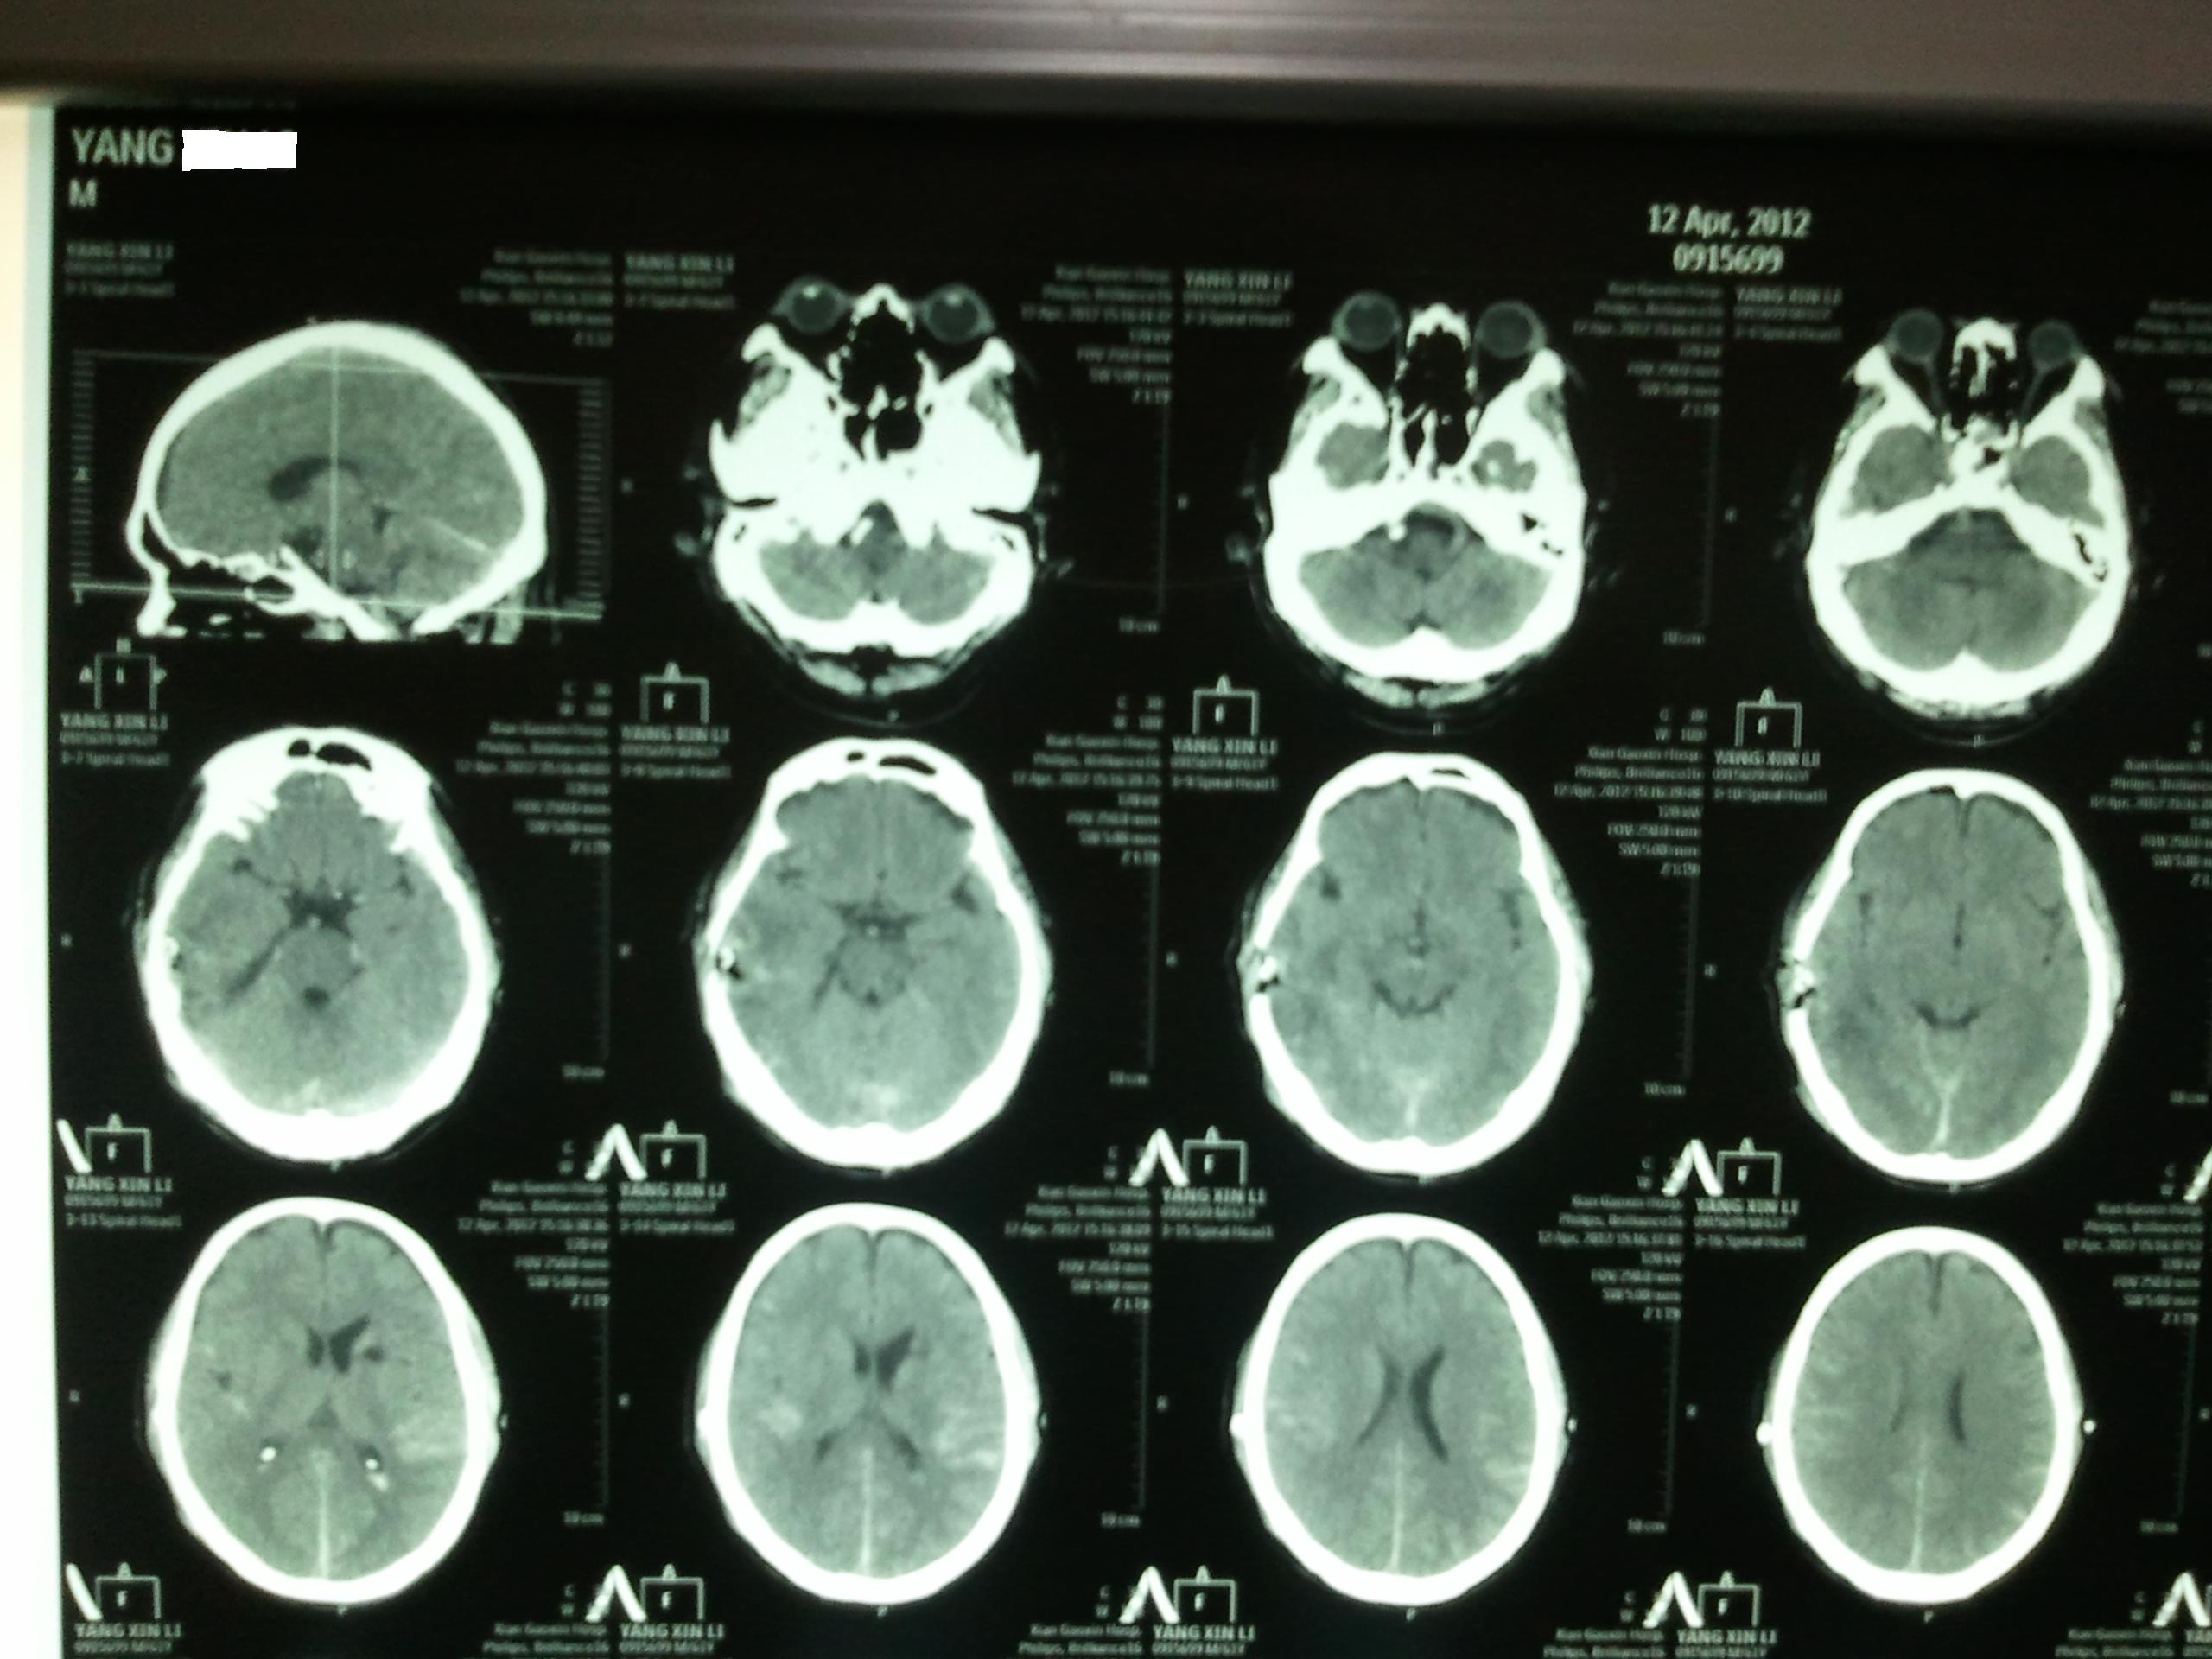

患者楊某,男性,61歲,以“頭部外傷伴意識進行性加重7小時”急診入院。查體淺昏迷,GCS 10分,雙側(cè)瞳孔等大等圓,直徑約2.5mm,光反應(yīng)靈敏。左側(cè)肢體力弱,右側(cè)巴氏征陽性,左側(cè)巴氏征未引出,克氏征(+)。顱腦CT觀片右側(cè)顳葉高密度影,出血量約30ml。暫給予保守治療。入院48小時,患者意識加重,呈中度昏迷,GCS 7分,右側(cè)瞳孔較左側(cè)略大,光反應(yīng)遲鈍。雙肺呼吸音粗,左下肺可聞及濕羅音,復(fù)查頭顱CT平掃示右顳葉腦內(nèi)血腫較前略增加,周圍低密度水腫區(qū)較前明顯擴大,右側(cè)側(cè)腦室及三腦室受壓明顯,中線左偏。胸部CT提示雙側(cè)少量胸腔積液。β-羥基丁酸3.93mmol/L,血乳酸5.23mmol/L,尿常規(guī):葡萄糖(+++),蛋白(+++),酮體(+++),末梢血糖最高達24.0mmol/L,血常規(guī):WBC 15.61×109/L中性粒細胞81.70%。內(nèi)分泌專科診斷:2型糖尿病,糖尿病酮癥。呼吸科專科診斷:雙肺肺炎,Ⅰ型呼衰。

氣管插管全麻下右耳屏上1cm直行切口長約4cm,銑刀開小骨窗約2.5×2.5cm,十字切開硬腦膜并懸吊,冷光源吸引器吸除凝血塊及壞死腦組織,嚴(yán)密止血并反復(fù)沖洗硬膜下及血腫腔。腦受壓解除,搏動明顯。腦挫裂傷灶創(chuàng)面及血腫腔敷貼纖維速即紗一片止血。硬膜下血腫腔內(nèi)留置負壓引流一條,硬腦膜復(fù)位。硬腦膜外鋪明膠海綿兩片防止腦脊液漏。術(shù)畢,手術(shù)時間60分鐘,術(shù)中出血約30ml。術(shù)后患者清醒。術(shù)后第三天復(fù)查顱腦CT,觀片腦挫裂傷及腦內(nèi)血腫完全清除。聯(lián)合內(nèi)分泌、呼吸科給予綜合治療。術(shù)后6天拆線,10天出院。術(shù)前、術(shù)后、骨窗CT及頭皮手術(shù)切口見圖(a為術(shù)前CT,b為術(shù)后CT,c為骨窗CT,d為手術(shù)切口)。